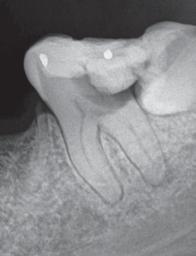

Do I really need to remove my wisdom teeth, they don’t hurt?

Through the studies of ancient tribes there was a time where one’s jaws were big enough to accommodate 32 teeth. Through environment and dietary changes we no longer have room for the third set of molars, also called wisdom teeth. When these teeth cannot erupt in to the mouth correctly they often become “impacted” or stuck in a crooked position. This impaction causes several problems which are not always painful including:

• Damage to other teeth: by crowding and pushing other teeth causing pain and bite problems

• Jaw damage: cysts can form around the third molars causing bone loss and damage to the nerve

• Cavities: swollen, infected gums can create pockets between teeth that help bacteria form and cavities will develop

The jaw bone has no feeling other than the nerve that runs through it and connects to teeth from under the roots; unless your problem affects the actual nerve you may have no pain but that does not mean there is no problem-not yet!

Misaligned wisdom tooth that caused patient to lose both teeth. Impacted Wisdom teeth.